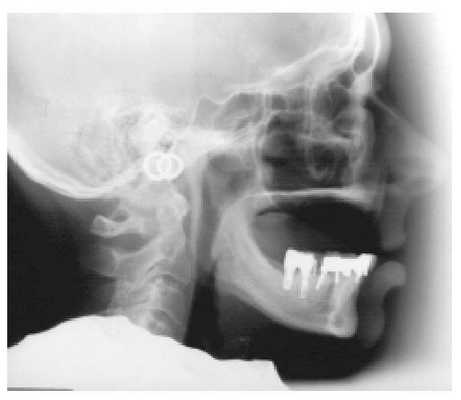

Биомеханика и окклюзия при полном протезировании

У многих пациентов, страдающих от полной адентии обеих челюстей долгое время, часто наблюдается прогрессирующая потеря костной ткани, в условиях которой дентальные имплантаты можно установить только в переднем отделе нижней челюсти между ментальными отверстиями. Съемные конструкции протезов, особенно те, которые не поддерживаются зубами, обеспечивают сомнительный уровень стабильности во время функционирования.

При восстановлении окклюзионных схем следует учитывать специфику дизайна протеза: поддерживается ли он собственными зубами или имплантатами, или же полностью ложится на слизистую костного гребня. Площадь поверхности конструкции, влияние атмосферного давления, форма резидуального гребня и особенности его морфологии, наличие ретенционных элементов, механические параметры опоры, а также факторы, способствующие смещению протеза, являются теми критериями, учет которых просто обязателен для обеспечения эффективных результатов стоматологической реабилитации.

Фото 1. Пациент с дефицитом костной ткани, ограничивающим возможность установки имплантатов.